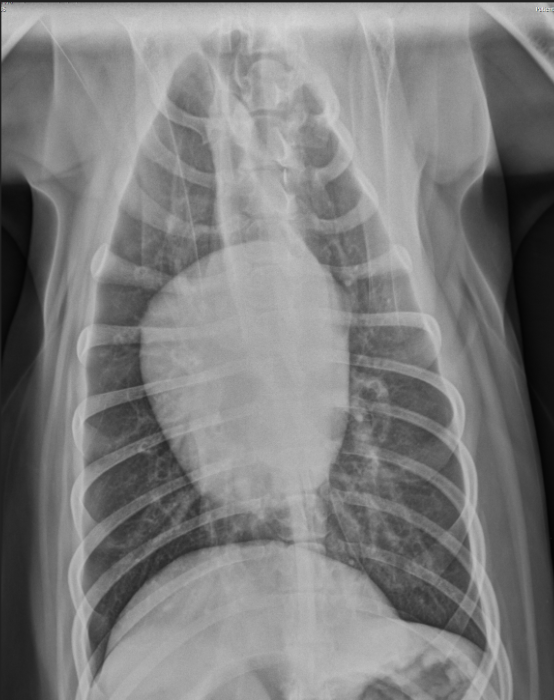

What heart condition?

4 ddx?

globoid cardiomegaly

pericardial effusion

dilated cardiomyopathy

peritoneal pericardial diaphragmatic hernia

severe tricuspid valve disease